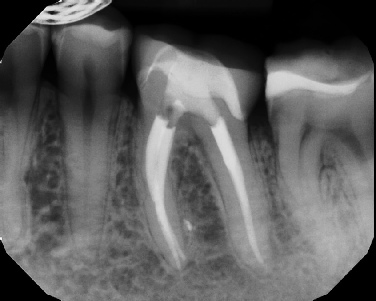

COMPLICATED ANATOMY LARGE LESIONS CALCIFIED CANALS PERFORATION / RESORPTION SEPARATED INSTRUMENTS SURGICAL CASES RETREATMENT / pOST REMOVAL OPEN APICES ACCESS THRU CROWNS Root Canal Case Portfolio

Pre-op Post-op 6 mos.